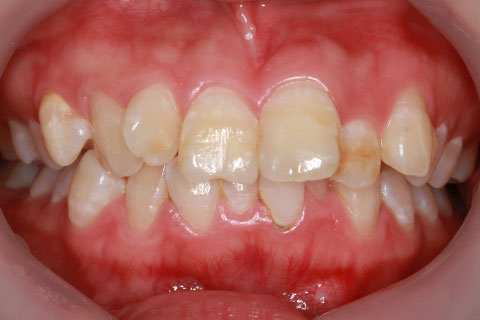

治療前

- 年齢・性別

- 25歳女性

- 治療期間

- 2年0ヶ月

- 抜歯

- 上下4番抜歯

- 治療費

- 110万円

- 治療内容

- 施術の副作用(リスク)

- 表側矯正と比較して、力学的な操作性が複雑なため、ボーイングエフェクトを起こしやすい。